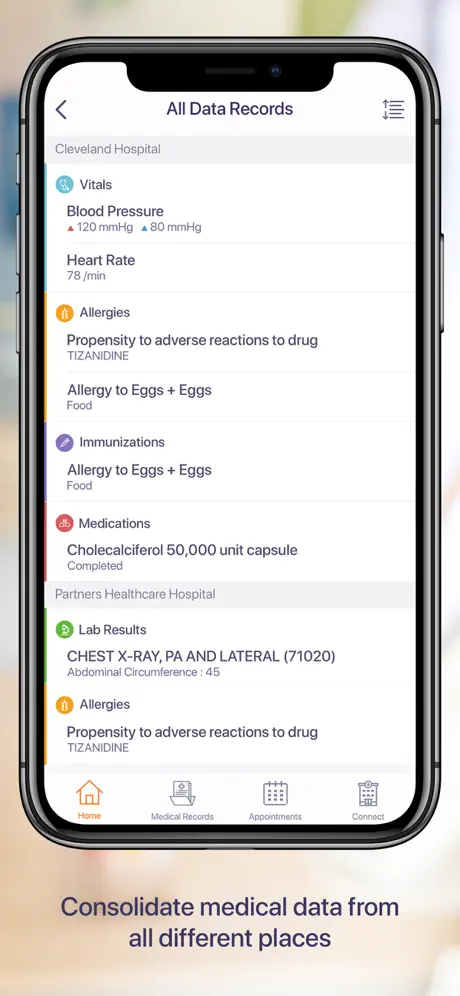

CarePassport es una plataforma universal de próxima generación que ofrece a los pacientes un punto de acceso único para recolectar, almacenar, compartir y administrar sus citas y registros médicos.

La aplicación permite a los pacientes acceder de forma segura a sus datos médicos o proxies familiares, programar citas, ver imágenes médicas, informes clínicos y de laboratorio de diferentes proveedores con la capacidad de descargar, archivar y compartir utilizando la tecnología de computación móvil más avanzada.

- Acceso fácil y rápido a los datos de su salud

- Integración con el sistema EMR / PACS dentro de las organizaciones sanitarias para captar datos de pacientes